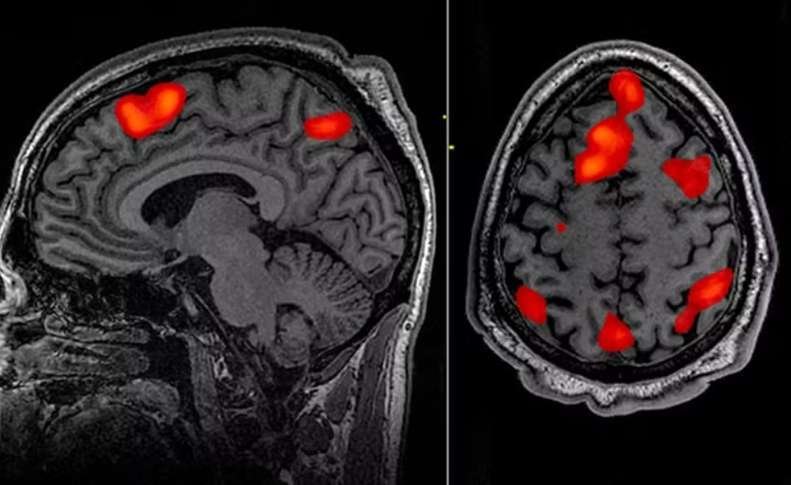

A doença de Huntington é causada por uma mutação no gene da huntingtina, que leva à produção de uma proteína tóxica para os neurônios. A condição provoca perda progressiva de funções motoras, cognitivas e comportamentais, resultando em dependência e morte, geralmente em até 20 anos após o início dos sintomas.